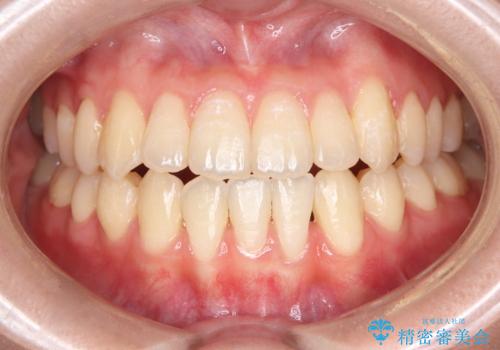

突き出た前歯を下げて理想的な横顔に。上下左右4番抜歯による審美ワイヤー矯正

担当医 河口智英